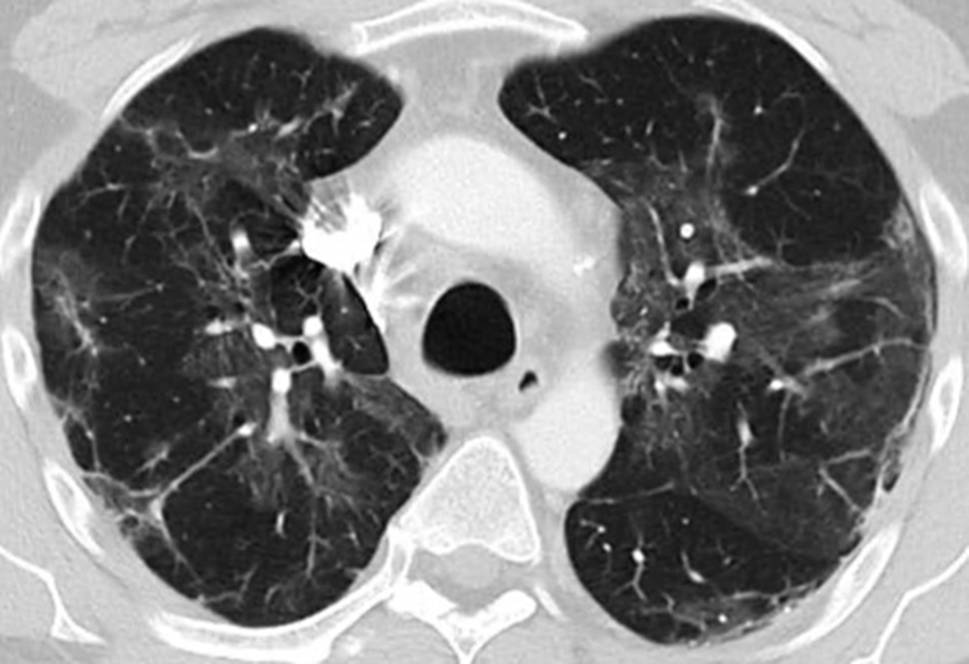

Fig. 2

Lung CT scan in the upper lobe 4 weeks after symptom onset showing patchy subpleural ground glass opacities and linear consolidation

His fever disappeared but he remained substantially short of breath during minor exertion. Suspecting Covid19 he saw a pulmonologist on 15 April. Physical findings were unremarkable and the chest X‑ray showed interstitial opacities with subpleural reticular densities predominantly in the lower fields (Fig. 1). On 20 April the computed tomography (CT) scan showed subpleural patchy ground glass opacities predominantly in the upper lobes (Fig. 2). The lower lobes in addition to ground glass showed arcade-like bands of parenchymal consolidation, peribronchial consolidation and mild bronchiolectasis (Fig. 3). The CT pattern was suggestive of organizing pneumonia. He was referred to the pneumology department for further diagnostic work-up.